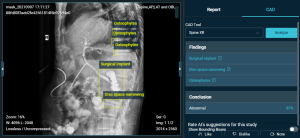

3.2. AI hỗ trợ chẩn đoán hình ảnh

Việc phân tích hình ảnh y khoa (X-quang, MRI và CT scan) yêu cầu y bác sĩ phải có kỹ năng và sự tập trung cao. Tuy nhiên, với cường độ công việc dày đặc mỗi ngày, y bác sĩ có thể mắc sai lầm. Do đó, một hệ thống AI để hỗ trợ chẩn đoán hình ảnh là điều cần thiết.

AI sử dụng công nghệ deep learning để phân tích hình ảnh y khoa, giúp phát hiện các bất thường mà có thể bị bỏ qua bởi con người. Đại học Stanford University (Mỹ) đã phát triển CheXNet – một hệ thống AI sử dụng deep learning để phân tích hình ảnh X-quang ngực. CheXNet được huấn luyện trên 100.000 hình ảnh X-quang và có khả năng phát hiện 14 loại bệnh lý, bao gồm bệnh viêm phổi với độ chính xác đạt tới 94.5%, cao hơn các chuyên gia y tế.

Với sự chính xác và tốc độ chẩn đoán này, CheXNet đã giúp Stanford cải thiện quy trình chẩn đoán, giảm thời gian từ khi chụp hình ảnh đến khi đưa ra kết quả, từ đó giúp bệnh nhân nhận được điều trị kịp thời.